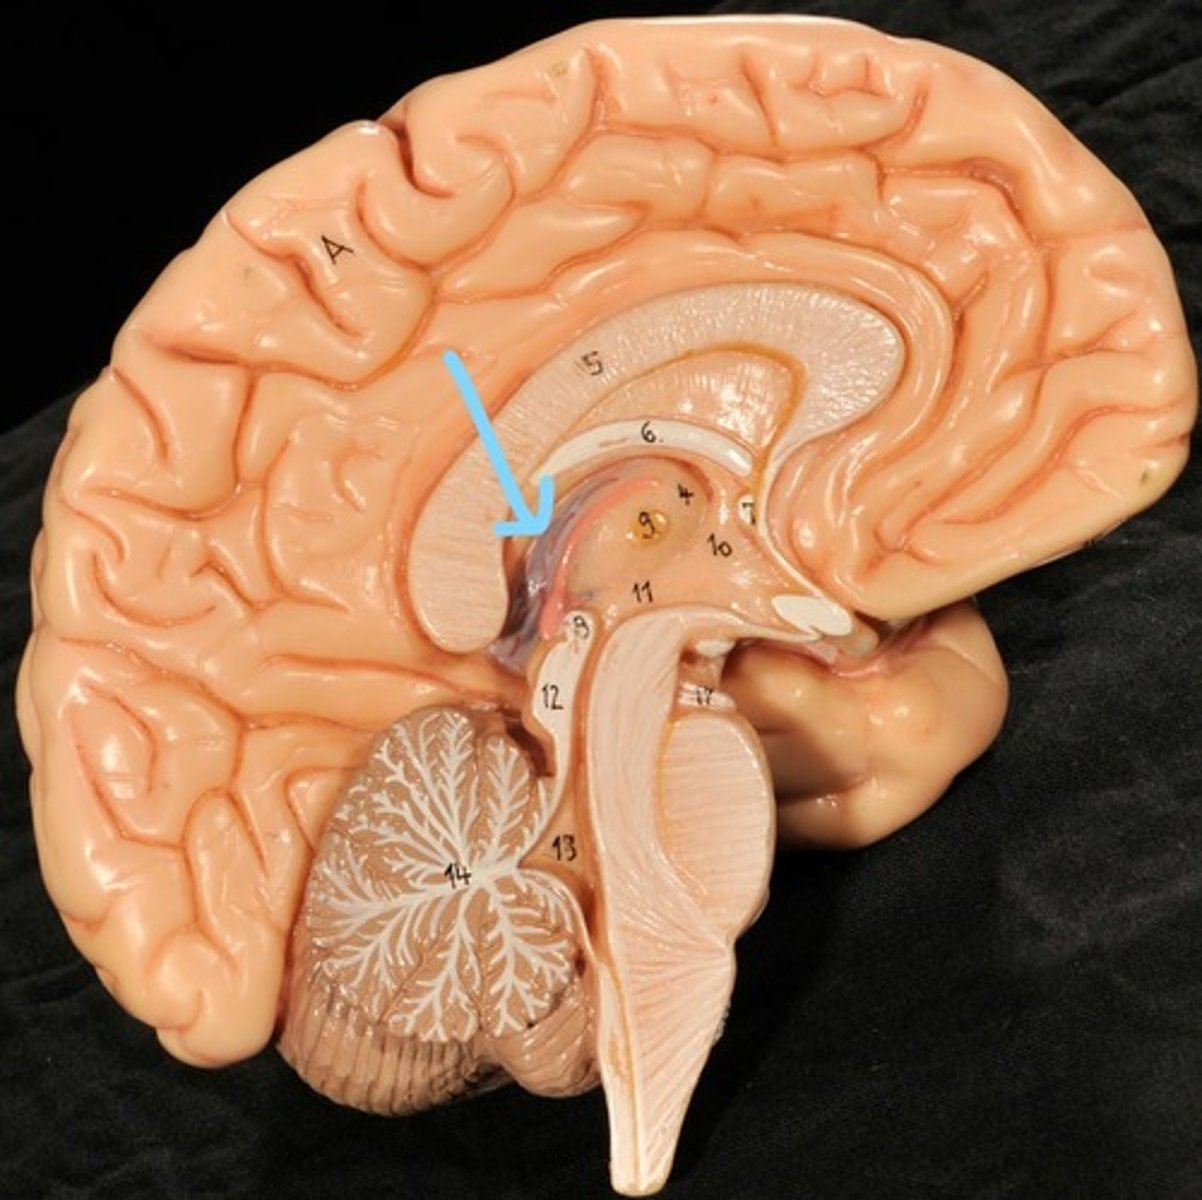

Identify structures of midsagittal brain

Corpus callosum

Diencephalon

thalamus, third ventricle, hypothalamus, epithalamus

Thalamus

Third Ventricle

Hypothalamus

Epithalamus (pink line)

Brain stem

Pons

Medulla oblongata

choroid plexus of third ventricle

produces cerebrospinal fluid

Third ventricle

cerebral aqueduct (midbrain)

midbrain

Fourth ventricle

Central Canal of brain

Takes Cerebrospinal fluid down to the spinal cord

Thalamus